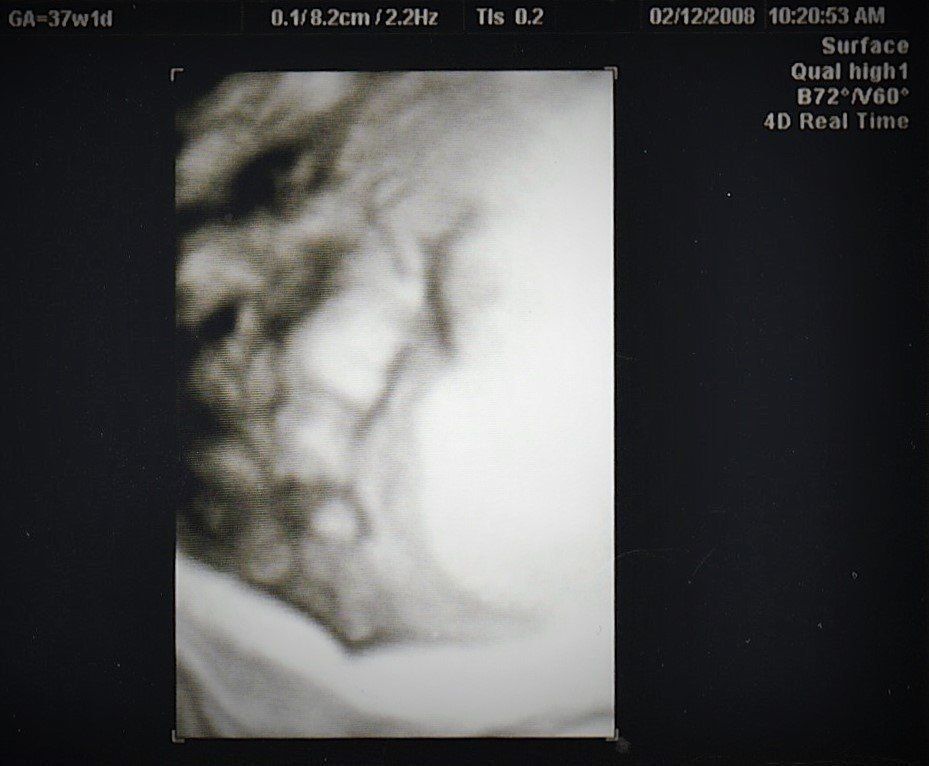

妊娠37週目のエコー写真

推定体重3000gにまで増えていてビックリ。私自身が2600gで生まれており、「お産は母親に似る」と聞いていたので、勝手に少し小さめで生まれてくると思っていました。「4000g超えになるかも」と不安を覚えました。私は既に10kg近く増加になっていたので、この時期から意識的に散歩と、食べすぎに気をつけ、臨月は赤ちゃんの増加分(約1kg)にとどめ、最終的に10.5kg増で抑えました。